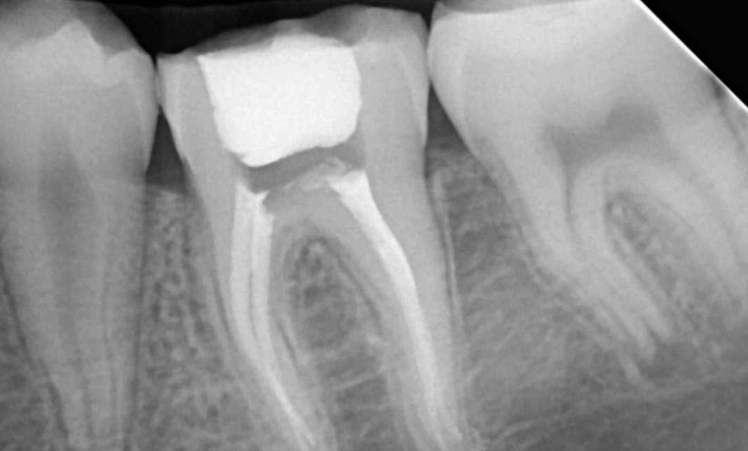

- More Roots and Canals: Front teeth might have one root. A molar can have two, three, or even four roots, each with one or more canals. Finding and cleaning all of them is a precise task.

- Complex Anatomy: The canals inside molar roots can be curved, narrow, or branch out in unexpected ways. It's like cleaning a intricate, microscopic cave system.

After the canals are cleaned, shaped, and dried, they need to be filled to prevent re-infection. A biocompatible material, usually a rubber-like substance called gutta-percha, is used to fill the space. It's sealed in place with a dental adhesive cement. The goal is to hermetically seal the root canal system.

- Missed Canals: Remember those complex molar anatomy? Sometimes a tiny, extra canal is missed during cleaning and remains infected.

- Incomplete Cleaning: Severely curved or blocked canals might not be fully cleaned.

- Poor Seal: If the filling material doesn't seal the tip of the root perfectly, bacteria can leak back in.